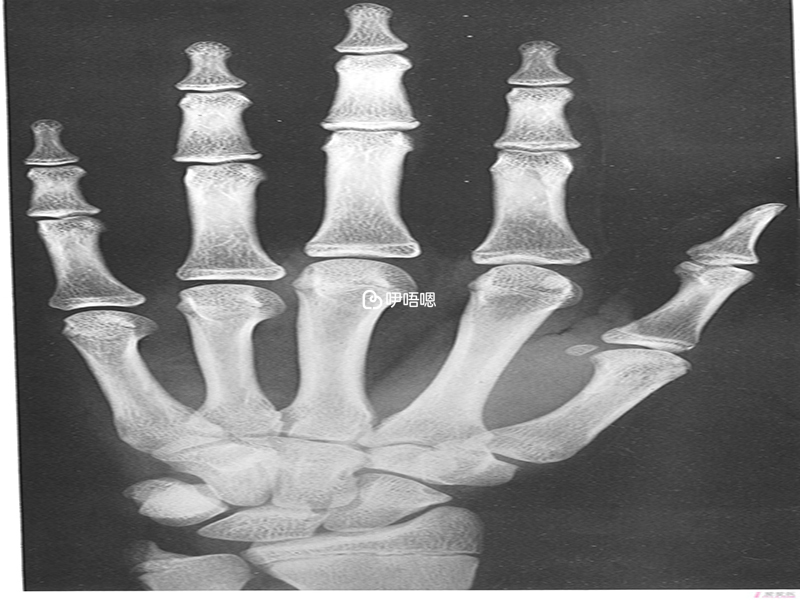

現在醫學技術發達,很多家長都會帶孩子到醫院檢測骨骼年齡,然後看孩子還有沒有繼續生長髮育的可能,而骨骼年齡也就是骨齡,通常是要拍攝人左手手腕部的X光片,醫生會通過X光片觀察左手掌骨、腕骨以及橈尺骨下端的骨化中心的發育程度,以此來確定骨齡。一般測骨齡需要花費20~30元,不過不同醫院、不同地區,收費的價格可能會有所浮動。

臨床上,醫生一般通過拍攝腕關節、肘關節、腰椎側位還有髂骨翼這幾個部位的x線平片來判斷骨齡,但是很多人都不知道如何簡單識別孩子的骨齡片,其實對於骨齡片的觀看,可以通過G-P圖譜法或者積分法來對患者的骨齡進行判斷,比如: